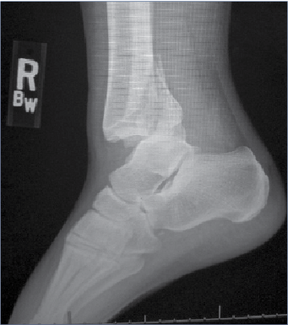

ankle

07/15/2023

Brian McCurdy

Distal fibula fractures, syndesmotic fractures, intramedullary fixation of fibular fractures, posterior malleolus repair, deltoid ligament repair, and ankle fractures in patients with neuropathy, fragility, and infection were hot topics at...